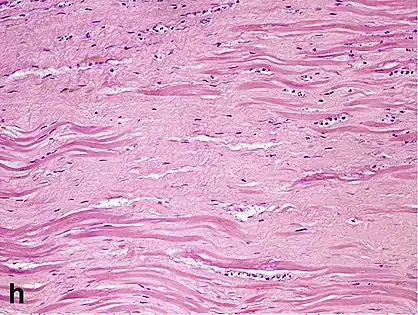

Interstitial fibrosis of chronic ischemic heart disease, H&E stain, with associated relatively well organized myocardial bundles Subepicardial fibrosis (epicardium at top).

Subepicardial fibrosis (epicardium at top). Replacement fibrosis in myocardial infarction, typically being boundless, dense and not conforming to the other types.